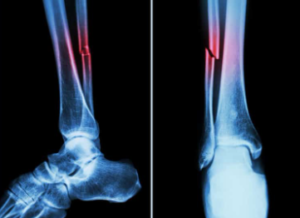

단순골절과 복잡골절의 차이는, 뼈가 피부를 찢고 있는지의 여부.

‘단순골절’은 골절된 뼈가 피부 밖으로 나오지 않은 것을 말한다. 한편 ‘복잡골절’은 골절된 뼈가 피부를 뚫고 바깥쪽으로 나와 있는 상태를 말한다. 따라서 접히는 방식이 단순해도 피부에서 튀어나오면 복잡골절, 접히는 방식이 복잡해도 피부가 멀쩡하지 않으면 단순골절인 것이다.

각기 다른 호칭이 있는데 ‘단순골절’은 ‘폐쇄골절’, ‘복잡골절’은 ‘개방골절’이라고 한다. 이쪽이 상상하기 쉬울 것이다. 피부가 닫혀 있느냐 열려 있느냐 하는 것이다.

복잡골절 또는 개방골절의 경우에는 뼈가 외부로 나와 있어 감염 가능성이 높고, 감염병을 병행하면 낫기가 어려워진다. 단순골절 또는 폐쇄골절의 경우 감염 가능성은 낮고 뼈 교정만 하면 된다.